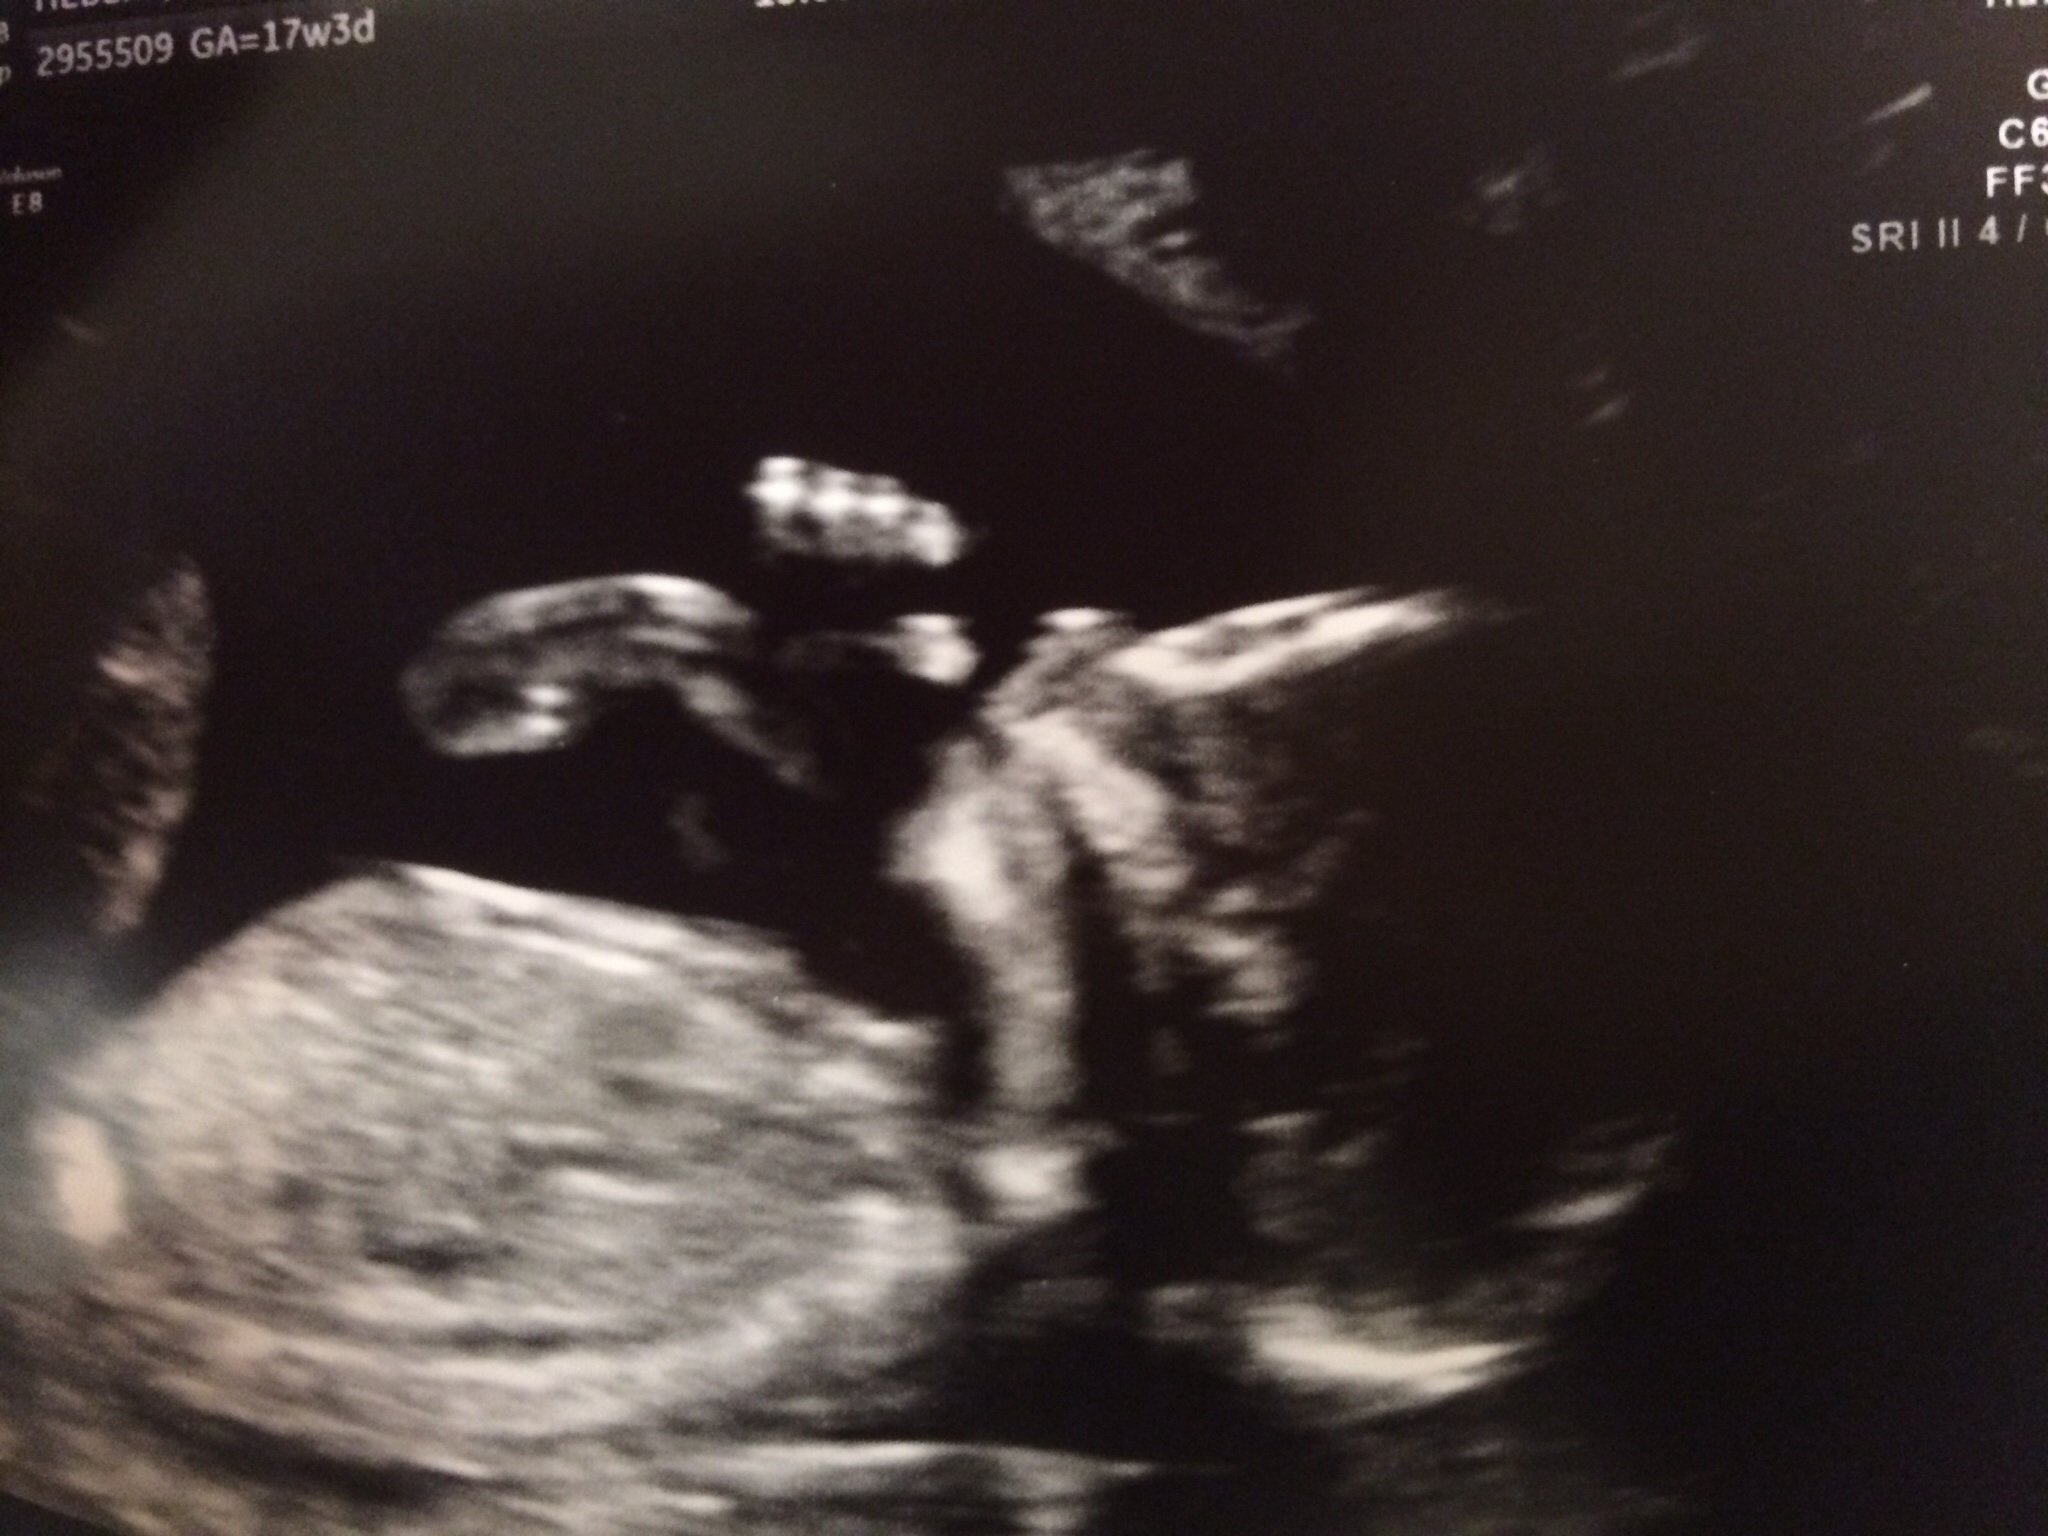

I`m freaking out... PGAL brain kills me. I don`t know how I`m going to sleep this night.

image

BabyFruit Ticker

imageimageimage

Baby# 1 - gone at 6 weeks - Oct 2009

Baby# 2 ( beloved girl Maria) -stillbirth at 31 weeks - Apr 2013

Baby# 3 EDD April 2014 - Hope it`s our take home baby

*sorry for grammar mistakes, I learned english pretty much by myself.